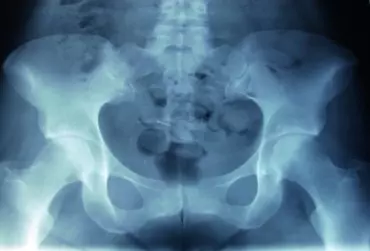

Staw krzyżowo-biodrowy

Zdecydowana większość zaburzeń w obrębie stawów krzyżowo-biodrowych jest konsekwencją codziennych nawyków bądź asymetrii prawej i lewej strony ciała (lateralizacji). Przeważnie dysfunkcje te związane są z nawykami, takimi jak spanie na jednym boku, bądź zakładanie nogi na nogę. Z biegiem czasu efektem nawyków mogą być zaburzenia równowagi mięśniowej, które objawiają sięprzykurczami, ograniczoną ruchomością oraz zaburzeniami postawy ciała [1].

Diagnostyka stawu krzyżowo-biodrowego dla potrzeb fizjoterapii

Dolegliwości bólowe okolicy lędźwiowo-krzyżowej są objawem niespecyficznym i właściwym dla wielu jednostek chorobowych [1]. Określenie jednoznacznej etiologii jest trudne z powodu występowania zespołu nakładania bądź istnienia ścisłych zależności patogenicznych pomiędzy jednostkami chorobowymi wchodzącymi w skład wymienionych grup [2]. Dlatego też w procesie stawiania prawidłowej diagnozy wysuwa się

przeprowadzenie rzetelnego badania przedmiotowego i podmiotowego oraz diagnostyki różnicowej. Celem niniejszego artykułu jest przedstawienie diagnostyki stawu krzyżowo-biodrowego dla potrzeb fizjoterapii.